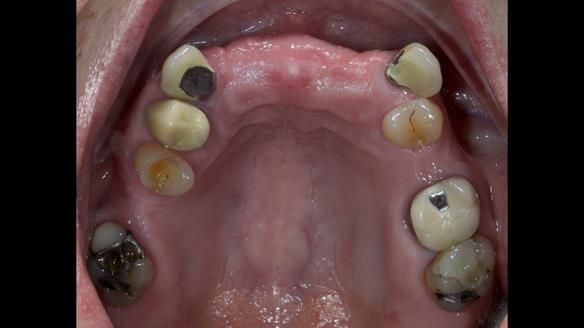

This is one of those cases that reminds me why I love removable prosthodontics. Pam was an absolute joy to treat — we were on the same page throughout. Her old upper flexible denture was loose, uncomfortable, and unaesthetic. We replaced it with a carefully designed metal-based upper partial denture/splint and new porcelain-bonded-to-zirconia (PBZ) crowns for the canines. The result is stable, comfortable, and natural-looking.

- Diagnosis and plan – Flexible upper denture ill-fitting with poor stability, retention, and appearance. Plan: metal-based upper partial denture/splint with lighter porcelain-bonded-to-zirconia crowns on UR3 and UL3.